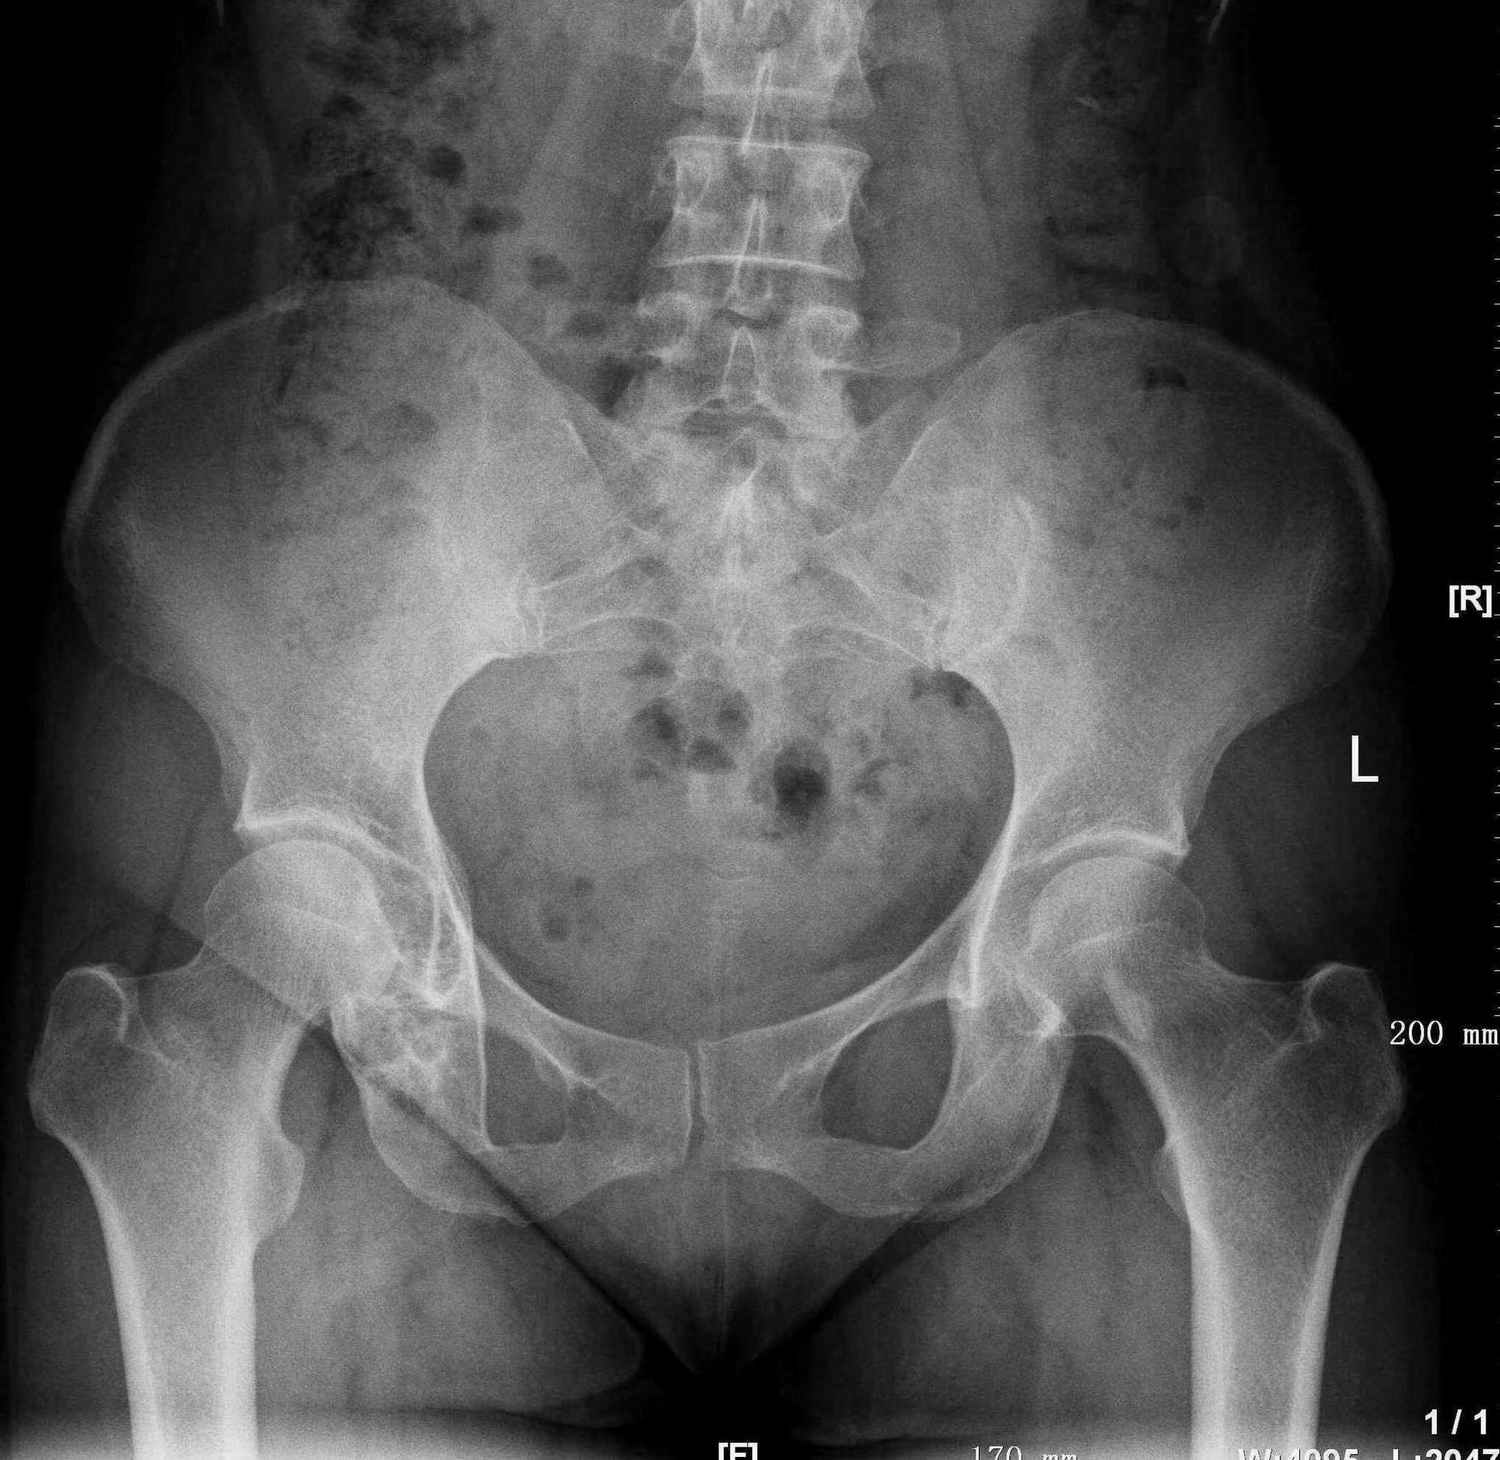

标题: X6296:右侧髋臼、右侧耻骨病变,无外伤,从小已发现,无明 [打印本页]

标题: X6296:右侧髋臼、右侧耻骨病变,无外伤,从小已发现,无明

右侧髋臼及坐骨支病变考虑软骨母可能性大,其次骨纤及内生软骨瘤不排除。左侧股骨颈骨岛。

右坐骨上支膨胀性改变,考虑骨纤可能性大

考虑右侧坐骨上支近髋臼处骨纤维异常增殖症。

右坐骨上枝及髋臼下缘呈膨胀性骨质破坏,考虑骨纤可能,左股骨颈骨岛。